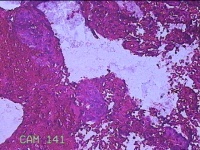

宫颈管内组织

性别

女

年龄

46岁

临床诊断

异常子宫出血

一般病史

阴道流血伴血块6天。

标本名称

大体所见

灰白暗红色不规则碎组织1.5x1.3x0.3cm一堆。

图1